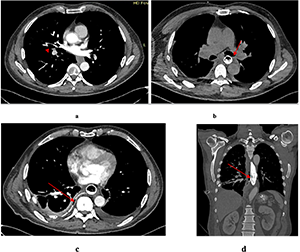

Figures 1 and 2 present the determined intensive indicators of primary disability due to ACS in Ukraine, calculated per 10 thousand population for the period of 2011-2024 among the adult and working-age population, respectively. The prevalence rate of primary disability among the adult population of Ukraine due to the consequences of ACS was: 1.9 per 10 thousand population in 2011; 1.6 – in 2012; 1.8 – in 2013; 1.7 – in 2014; 1.6 – in 2015; 1.5 – in 2016; 1.6 – in 2017; 1.8 – in 2018; 1.6 – in 2019; 1.3 – in 2020; 1.5 – in 2021; 2.1 – in 2022; 3.1 – in 2023, and 3.1 – in 2024.

Thus, a stable dynamics of the prevalence rate of primary disability among the adult population during 2011-2019 was revealed – from 1.9 in 2011 to 1.6 in 2019. During this period, the rate averaged 1.67 per 10 thousand people. It is important to note that well-known Ukrainian epidemiological studies on the “consequences of stroke”, which were the cause of primary disability over the period of 2002-2012 in Ukraine also determined a certain stable dynamics and were, respectively: 10.3; 10.3; 9.4; 10.7; 12.3; 10.6; 9.3; 9.0-10.1; 9.7 people per 100 thousand adults[18]. Other researchers also determined the absence of significant changes in the rate of primary disability due to ACS among the adult population in 2008-2010, which was 10.6-9.3-9.9 cases per 100 thousand people [17]. In our study, the minimum prevalence rate of primary disability among the adult population was determined in 2020, which was 1.3 per 10 thousand people, with a slight increase in 2021 to 1.5 per 10 thousand people. A significant increase in the indicator was found during the martial law period, when the indicator grew from 2.1 in 2022 to 3.1 in 2023-2024. The increase in the indicator during the war years grew by 1.6 times (+51.6%) compared to the stable period. The average annual growth rate (Δ) for the studied period was 0.277 or 27.7% per year.

The prevalence rate of primary disability of the working-age population due to the consequences of ACS in Ukraine in 2011 was 2.4 per 10,000 population, in 2012 – 2.2; in 2013 – 2.3; in 2014 – 2.3; in 2015 – 2.1; in 2016 – 1.9; in 2017 – 2.0; in 2018 – 2.1; in 2019 – 2.0; in 2020 – 1.7; in 2021 – 1.9; in 2022 – 2.7; in 2023 – 3.4 and in 2024 – 2.5.

Among the working-age population, the results of the study revealed a stable dynamics of the prevalence rate of primary disability during 2011-2019 – from 2.4 in 2011 to 2.0 in 2017-2019. During this period, the rate averaged 2.4 per 10 thousand people. The minimum rate of primary disability among the working-age population was determined in 2020, being 1.7 per 10 thousand people, with an insignificant increase to 1.9 per 10 thousand people in 2021. During the period of martial law in 2022-2024, a significant increase in this rate among the working-age population was detected, which rose to 3.4 per 10 thousand people in 2023. At the same time, the increase in the indicator during the war years was 1.7 times (+50%) as compared to the stable period. The average annual growth rate (Δ) for the studied period was 0.094 or 9.4%.